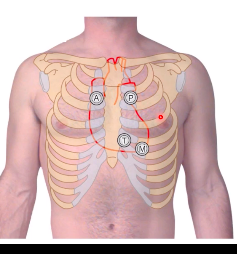

A = aortic valve P = pulmonary trunk valve T = tricuspid valve M = mitral valve